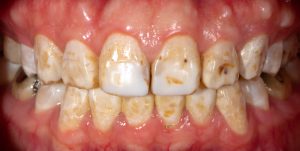

Enamel Hypoplasia

Sometimes children’s teeth don’t develop enough enamel, creating thin spots, grooves, pits, or white/yellow patches. This is called enamel hypoplasia.

What enamel hypoplasia looks like:

- White, yellow, or brown spots or bands on teeth

- Grooves or indentations in the enamel

- Teeth that look pitted or rough

- Areas where the enamel seems thin or missing